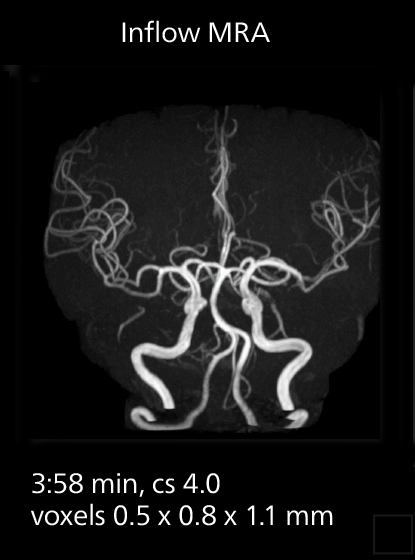

Fast whole body DWIBS examination

With SmartPath to Elition X the team can obtain excellent quality DWIBS imaging and reduce imaging time. Other sequences also fit in the examination slot. This case shows left paravertebral neurogenic tumor and Th10 vertebral hemangiomas.

The value of the Elition X gradients is also evident in DWIBS studies. “The fact that we can consistently obtain distortion‐free DWIBS while reducing imaging time at three coronal stations is excellent,” Dr. Makuuchi says. “In these patients, it’s also important that the application of Compressed SENSE to T2‐weighted, STIR and mDIXON sequences has no impact on the examination time of whole‐body imaging. As a result of the increased speed and higher image quality we realize, DWIBS studies have now become routine examinations.”